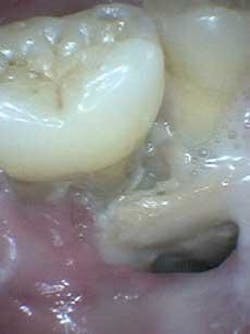

It was adenocarcinoma, a three–cm lesion bilaterally set in the anterior portion of his tongue. Two teams of surgeons, following a submandibular track, took 12 hours to remove the lesion by resecting the entire anterior tongue, then grafting a portion of his thigh to replace it. Intense radiation and chemotherapy followed. This shrank the new tongue to nothing, precipitated osteoradionecrosis, but gave him life.